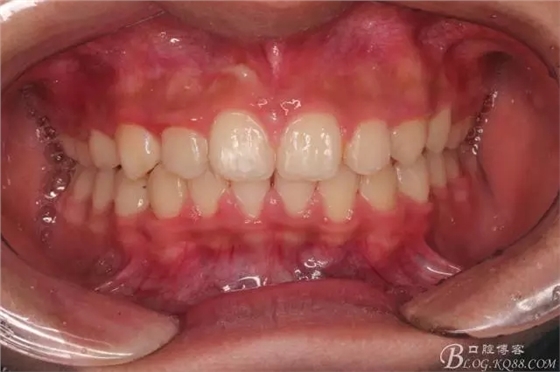

一晃快兩年了,我覺得關(guān)節(jié)重建及咬合穩(wěn)定,再加上患者的急迫愿望,我們拆除了矯正器。

尖牙關(guān)系中性,磨牙關(guān)系中性,咬合鎖結(jié)良好!

15歲了,1米78的個(gè)頭,陽光帥氣的他,側(cè)貌堪比天安門國旗手的面型?。釘懒耍?p style="text-align: left;">640.webp (24).jpg